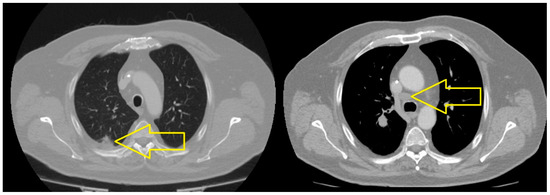

2. Case Presentation